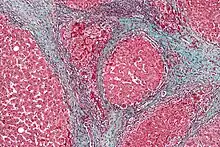

There are various explanations why liver dysfunction or portosystemic shunting might lead to encephalopathy. In healthy subjects, nitrogen-containing compounds from the intestine, generated by gut bacteria from food, are transported by the portal vein to the liver, where 80–90% are metabolised through the urea cycle and/or excreted immediately. This process is impaired in all subtypes of hepatic encephalopathy, either because the hepatocytes (liver cells) are incapable of metabolising the waste products or because portal venous blood bypasses the liver through collateral circulation or a medically constructed shunt. Nitrogenous waste products accumulate in the systemic circulation (hence the older term "portosystemic encephalopathy"). The most important waste product is ammonia (NH3). This small molecule crosses the blood–brain barrier and is absorbed and metabolised by the astrocytes, a population of cells in the brain that constitutes 30% of the cerebral cortex. Astrocytes use ammonia when synthesising glutamine from glutamate. The increased levels of glutamine lead to an increase in osmotic pressure in the astrocytes, which become swollen. There is increased activity of the inhibitory γ-aminobutyric acid (GABA) system and the energy supply to other brain cells is decreased. This can be thought of as an example of brain edema of the "cytotoxic" type.[13]

The diagnosis of hepatic encephalopathy can only be made in the presence of confirmed liver disease (types A and C) or a portosystemic shunt (type B), as its symptoms are similar to those encountered in other encephalopathies. To make the distinction, abnormal liver function tests and/or ultrasound suggesting liver disease are required, and ideally a liver biopsy.[4][8] The symptoms of hepatic encephalopathy may also arise from other conditions, such as bleeding in the brain and seizures (both of which are more common in chronic liver disease). A CT scan of the brain may be required to exclude bleeding in the brain, and if seizure activity is suspected an electroencephalograph (EEG) study may be performed.[4] Rarer mimics of encephalopathy are meningitis, encephalitis, Wernicke's encephalopathy and Wilson's disease; these may be suspected on clinical grounds and confirmed with investigations.[8][15]